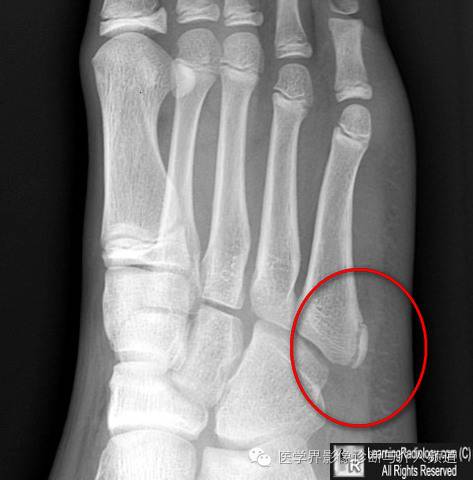

2、第5跖骨基底部骨骺:透亮线为纵行,与跖骨长轴平行。